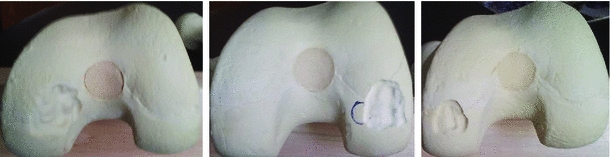

An alternative is mosaic arthroplasty (osteochondral implantation). In this procedure, the orthopaedic surgeon harvests joint cartilage from non-load-bearing parts of the joint and implants them at the damage site (the lesion) — analogous to filling a pothole.

Traditional mosaic arthroplasty is difficult: the surgeon must recreate the original joint surface near perfectly. If they insert plugs too high/proud, they shear off. If too shallow, the defect can fill with less desirable fibrocartilage instead of articular cartilage. If too large a gap is left below the plug, it can fill with fluid and form a cyst-like structure.

My work showed this method to be significantly more accurate (in customized bone models) than the conventional procedure, with reduced variance. The shortcoming is that it requires a more invasive opening of the joint cavity compared to the opto-electronic method.

Validation